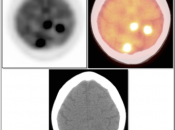

Brain Metastases:

- Far more common than primary lesions (> 10 times).

- If small and at grey-white junction, can be easily overlooked.

- Commonly from lung, breast, melanoma and GI primaries.

CNS Lymphoma:

- Usually very hypermetabolic (FDG uptake is often greater than high-grade gliomas or metastatic lesions).

- Association with immunocompromised status.